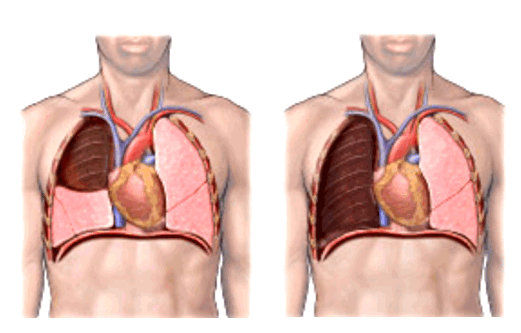

При лечении местнораспространенного злокачественного образования с переходом на главный бронх и лёгочную артерию, в тех случаях, где раньше единственным вариантом оперативного лечения являлась пневмонэктомия, сейчас возможно выполнение органосохранных операций. В этом случае иссекается пораженный участок главного бронха с последующим восстановлением непрерывности (бронхопластические и ангиопластические лобэктомии)

Фото 5 — Схема верхней бронхопластической лобэктомии

Рукавная лобэктомия - изъятие крупного очага онкологии, находящегося в главном или долевом бронхе. При ее проведении врач удаляет поврежденную часть дыхательного пути и сшивает оставшиеся ткани, находящиеся выше и ниже пострадавшего участка. Этот тип вмешательства может быть назначен как альтернатива пульмонэктомии, позволяющая сохранять максимум функций легких.

- Рукавная лобэктомия является альтернативой пневмонэктомии, когда злокачественная опухоль находится в главном или долевом бронхе. Хирург пересекает бронх выше и ниже пораженного участка и удаляет его. Затем соединяют оставшиеся концы.